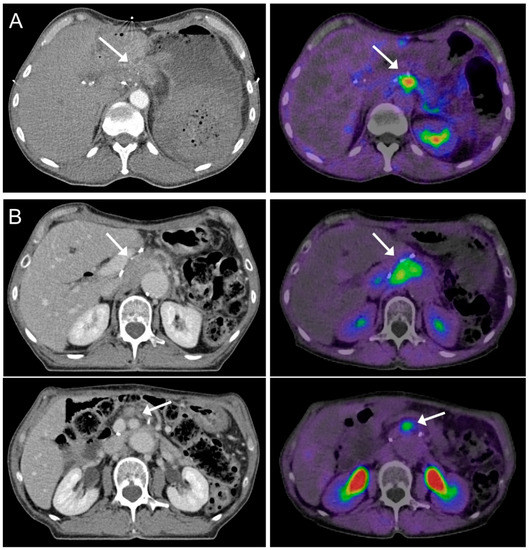

2.1. CT Imaging and Target Volume Definition by Radiation Oncologists

2.2. FAPI-PET/CT Imaging

3.2. Target Volume Definition by Radiation Oncologists

3.3. Interobserver Variability